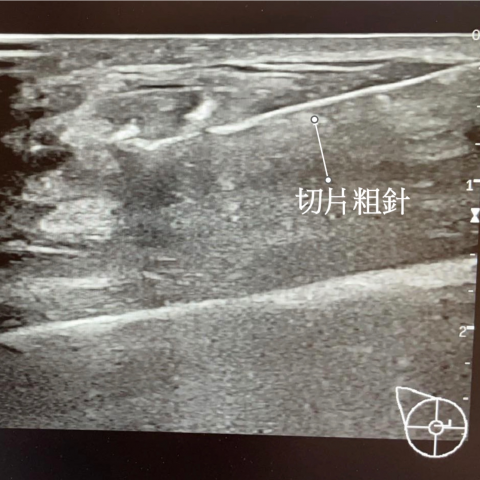

乳房硬塊切片檢查